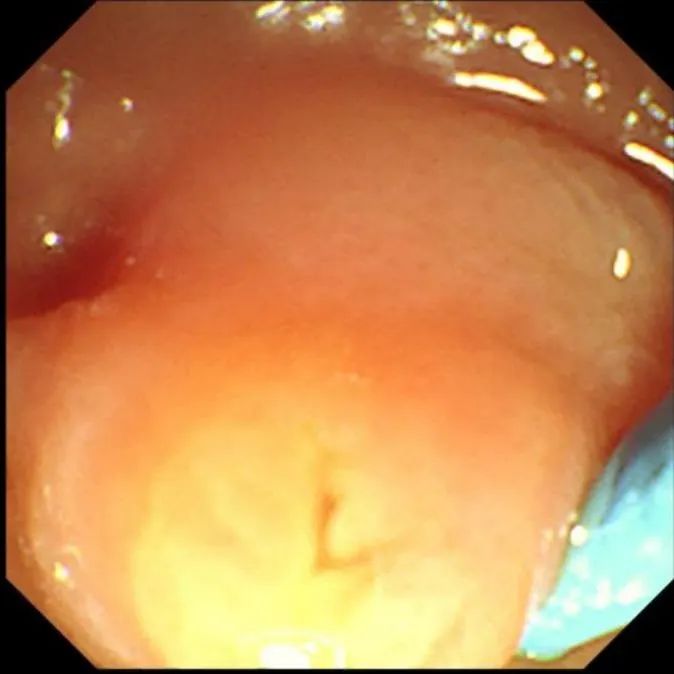

十二指肠乳头形态

图片